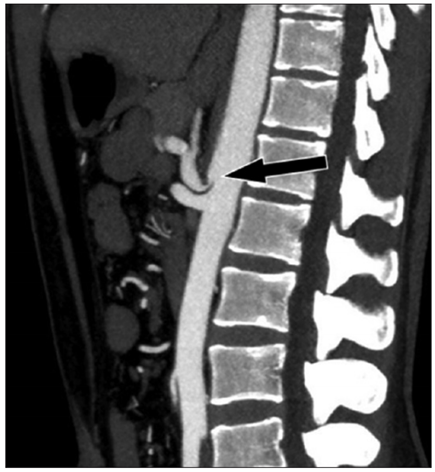

Vasos abdominais e pélvicos podem ser comprimidos por estruturas anatômicas que estejam próximas ou podem comprimir vísceras ocas adjacentes, por vezes caracterizando algumas síndromes de compressão vascular. O corte sagital de tomografia computadorizada (com contraste venoso) abaixo é de uma paciente de 25 anos, com queixas de dor epigástrica pós-prandial e perda de 8 kg nos últimos 2 anos.

Assinale a alternativa que contém o correto diagnóstico deste paciente.